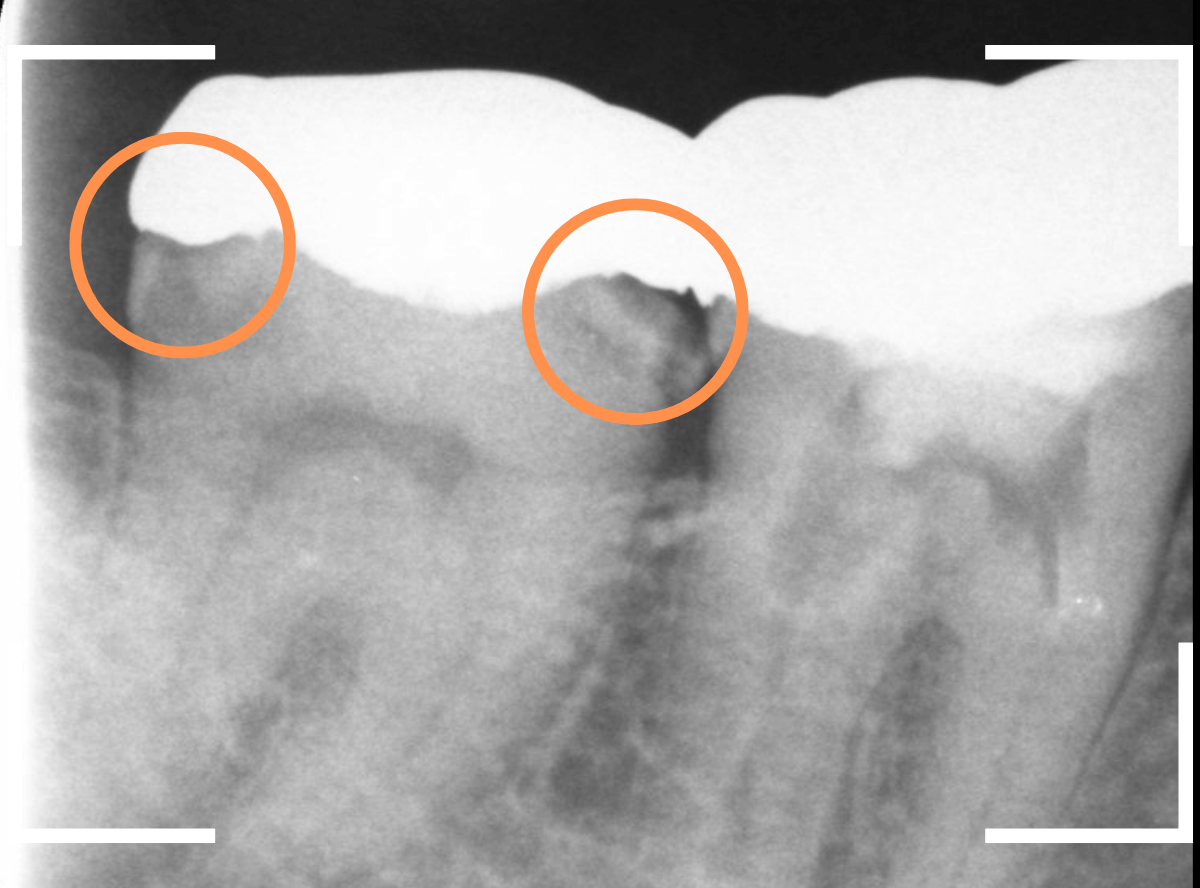

Case.18 おやしらずの抜歯後に歯がしみる

今回は、上のおやしらずが原因で虫歯になってしまった方のケースです。

〇部のおやしらずを虫歯で抜歯しました。

レントゲン写真です。

レジンの下が虫歯になっているのがわかります。

抜歯してしばらく経ったところです。

特に問題なさそうに見えますが、「おやしらずを抜歯してから、歯がしみるようになった」との訴えです。

これは、おやしらずを抜歯した後によくある症状です。

レントゲン写真で確認します。

青い線が歯の神経、赤い線が虫歯です。

おやしらずがあった際にはわかりづらかったですが、歯の後ろ側のおやしらずが重なっていたところが虫歯になっているのがわかります。

おやしらずが原因で、このように手前の歯が虫歯になってしまう事が多いために、抜歯を勧められる事が多いのです。

そして、虫歯の部分におやしらずが被さっていたために、しみる症状などを感じなかったのです。

金属を外したところです。

写真では写ってしませんが、この奥に虫歯があります。

全ての虫歯を除去したところです。

抜歯した後ろのおやしらずは、元々虫歯の治療がしてありましたが、その際に抜歯しておいた方が良かったのではないかな、と思いました。